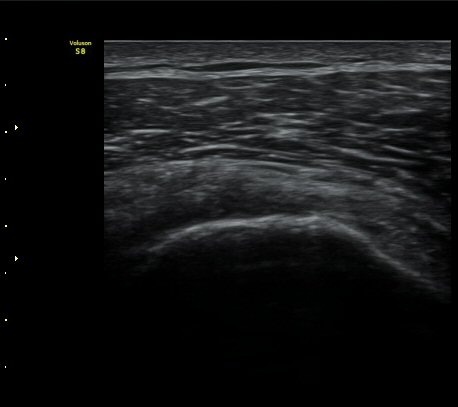

±Ø»ó°Ç Á¾´Ü¸é°Ë»ç½Ã ±Ø»ó°Ç ºÎÂøºÎ¿¡ Àú¿¡ÄÚ ºÎÁ¾°ú ¹Ì¼¼ÇÑ °Ç ¿¬°á¼º ¼Ò½ÇÀÌ

°üÂûµÊ (±×¸² 1, 2, 3 )